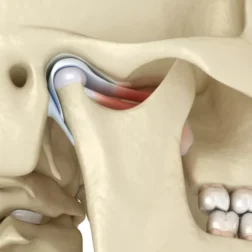

TMJ Surgery

Treats severe joint dysfunctions with minimally invasive techniques or joint prostheses.